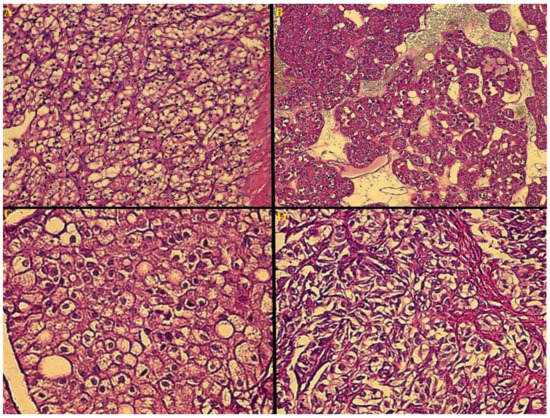

- Blastematous: diffuse, nodular and/or cord-like growth patterns of small, round and huddled blue cells, showing dark nuclei, diminished cytoplasm and frequent mitosis);

- Epithelial (tubules, papillae and glomeruli, similar to structures found in normal nephrogenesis, alongside more primitive rosette-shaped early tubular structures, and cysts lined with immature columnar/cuboidal cells);

- Stromal (resembling embryonal mesenchyme, spindle-shaped cells are seen on a myxoid stromal background, with a variety of patterns of differentiation and heterologous stromal elements, most commonly skeletal muscle in various stages of differentiation, including rhabdomyoblasts, but also cartilage, bone, fat or, more rarely, neuroglia and mature ganglion cells) [22,43].